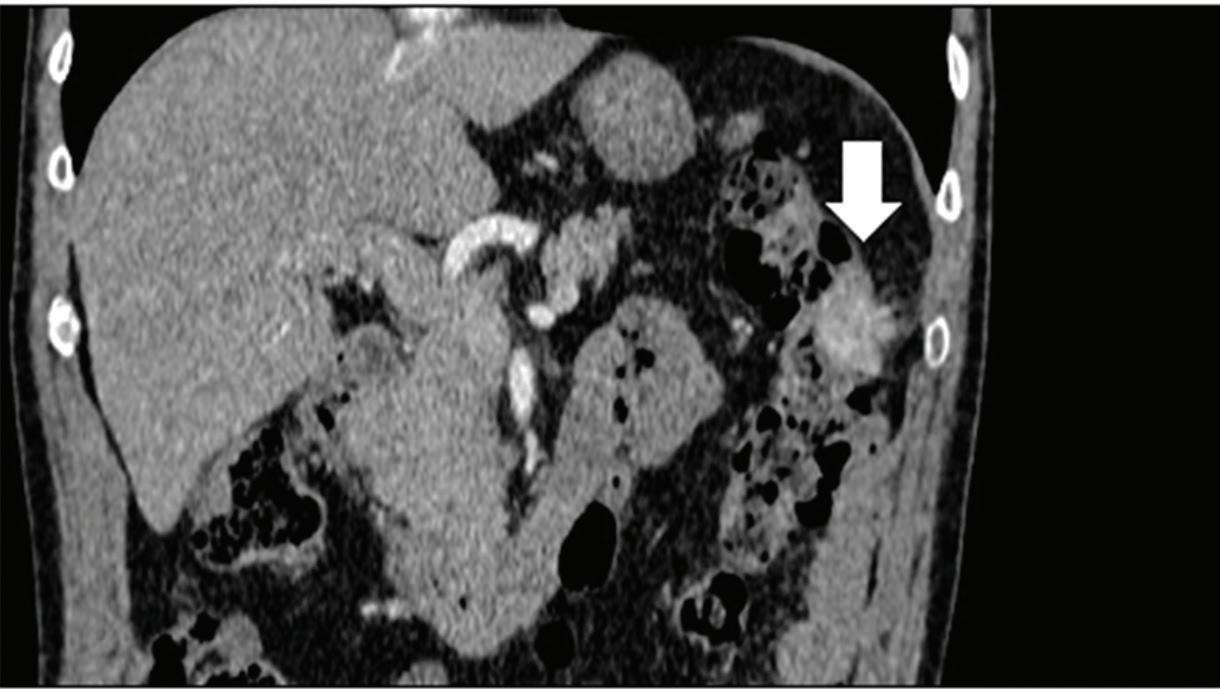

Z effective

Spectral CT is able to generate Z effective images that show the mean atomic number of the material present in a voxel (Z effective values) and can be displayed as color coded overlay maps. Z effective images may be helpful to enhance the visual differences between different tissue types.46 Furthermore, due to the high atomic number of iodine compared to other tissues present in the human body, the Z effective images can highlight enhancing structures (Figures 2, 3, 4, and 5) and could be used for quantitative analysis to differentiate benign from malignant tumors or lymph nodes.16,45,47

A small isoattenuating pancreatic adenocarcinoma (arrow), (a) which tend to blend into normal parenchyma on conventional axial CT image, acquired at pancreatic parenchymal phase with administration of 70 ml of contrast material (iodine concentration 350 mg/ml). (b) Monoenergetic 50 keV and (c) Z effective images improve detection by increasing conspicuity and contrast between tumor and normal parenchyma.

Pancreatic tumors. Several studies have demonstrated an obvious advantage of DECT for detection and staging of pancreatic adenocarcinoma using the low-monoenergetic data sets (Figure 5), regardless of the timing of the acquisition applied (single venous phase,55 pancreatic parenchymal phase,56 single split bolus single acquisition57).